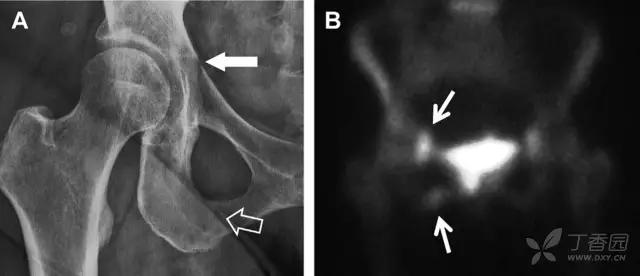

具有持续损伤因素的耻骨支骨折,可能看似轻微,尤其是合并骨质疏松的患者。因此,特别需要注意皮质缺损和骨密度改变。长跑运动员易发生耻骨应力性骨折,常常发生在靠近耻骨联合的下支。由于这些骨折为非移位骨折,所以常常被忽视。

图 3 自行车事故患者,侧方受力的髋臼前柱/耻骨骨折。A 正位平片示右侧髂耻线轻微中断(实箭头),此处异常最初并未发现。此外,右下方其实还有一处轻微耻骨支骨折(空箭头)。B 10 天后行骨闪烁显像证实了髋臼前柱骨折和侧耻骨下支骨折(箭头)。值得注意的是,左侧前柱亦存在异常